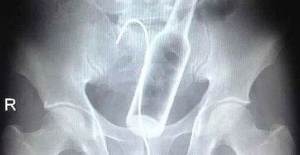

Doktorların görüp yok artık bu nasıl mümkün olur dedikleri röntgen filmleri..

Doktorluğun zor bir meslek olduğu malum. Üstelik bu mesleğin icra ederken bazı zamanlar öyle vakalar ortaya çıkmış ki, doktorlar bile anlamlandırmakta zorluk çekmişler.